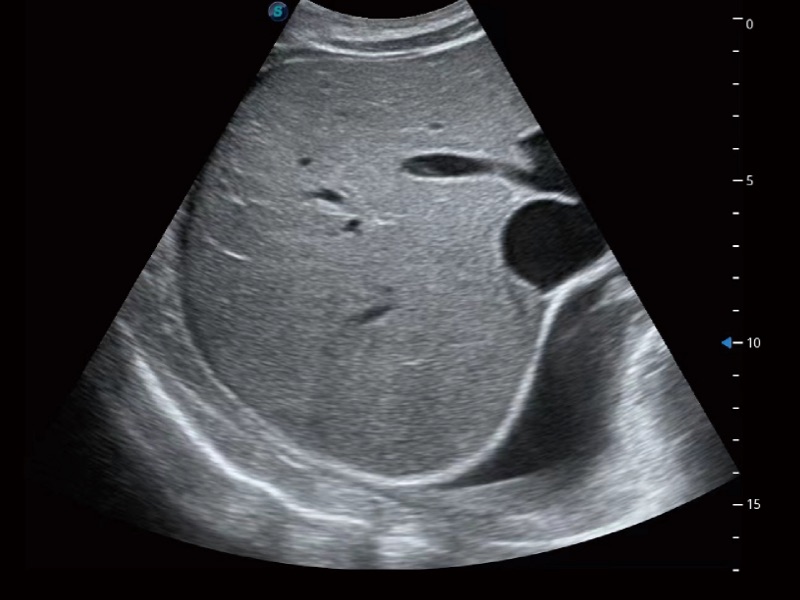

小器官应用

腹部应用